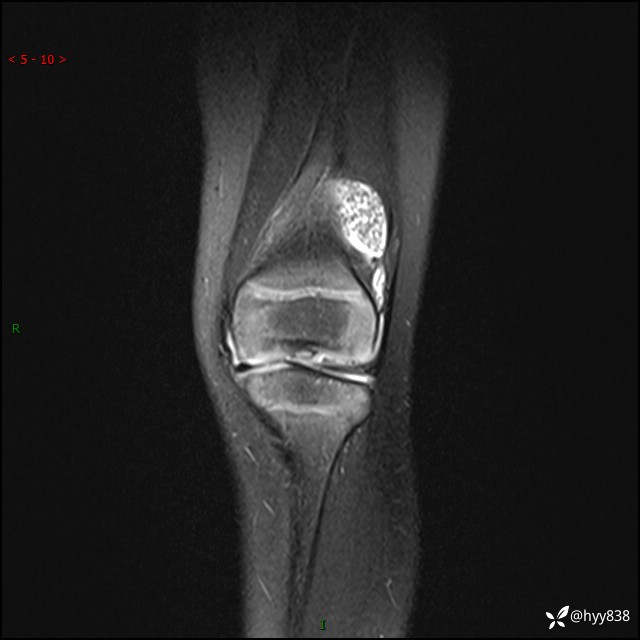

现病史:患儿1月前无明显诱因出现左下肢跛行,伴左膝关节红肿,无发热、咳嗽、恶心、呕吐等症,于当地医院就诊行X线片未提示异常,今至我院门诊就诊,门诊医师拟“跛行待查”收入院。 病后,患儿精神、食欲可,睡眠欠安,大小便通畅,体力体重无明显下降。

左膝MRI平扫